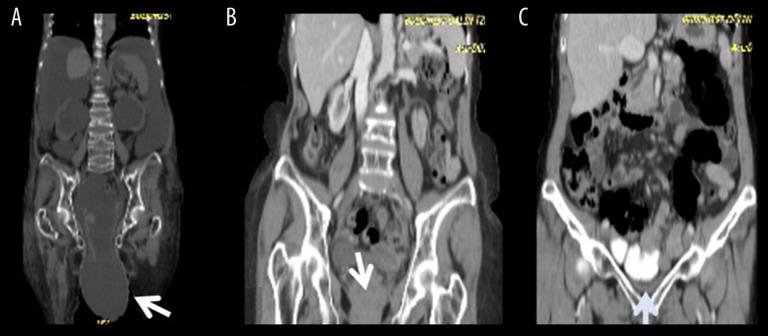

BACKGROUND Minimally invasive surgery (MIS) has rapidly advanced, but its use in transplant patients has lagged. We share our experience of MIS for patients after kidney and liver transplantation and compare our results with similar studies in the literature. MATERIAL AND METHODS This study included 14 MIS (12 laparoscopic, 2 transvaginal) procedures for 13 transplant cases (6 liver and 7 kidney) done from May 2006 to May 2018. Gastrointestinal surgery was performed in 6 cases: appendectomy performed 8 months after liver transplant and 16 months after kidney transplant in 2 cases, radical right hemi-colectomy performed 6 weeks after liver transplant in 1 case; exploration for chylous ascites 6 months after liver transplant in 1 case, sleeve gastrectomy performed 3 years after kidney transplant in 1 case, and partial hepatectomy performed 12 years after kidney transplant in 1 case. For urological problems, 2 patients received ipsilateral right-side nephroureterectomy performed 10 and 12 years after kidney transplant, and 1 patient received contralateral left-side nephroureterectomy performed 12 years after kidney transplant. The 2 liver transplant patients with huge incisional hernias received repair approximately 3 and 2 years after liver transplant. Three patients underwent gynecological surgery: 2 transvaginal for pelvic floor reconstruction in 1 patient with liver transplant and 1 hysterectomy in a kidney transplant patient, and 1 laparoscopic-assisted hysterectomy in a kidney transplant patient. We retrospectively analyzed the clinical presentation, operative findings, operation time, postoperative complications, and length of stay. RESULTS The postoperative course was uneventful, with early resumption of oral intake, including immunosuppressants administered the same as in the non-transplant patients. All surgical procedures in these transplant patients were achieved without conversion, showed stable kidney and liver function, had better surgical outcomes in comparison with traditional surgery, and most of them were discharged within 1 week. CONCLUSIONS Laparoscopic and non-laparoscopic MIS surgery are feasible and safe for abdominal organ transplant patients and are helpful for timely intervention in cases with acute abdomen. No adjustment of immunosuppressant is usually needed, as oral intake can be resumed very soon after surgery.

这项研究包括了 14 例 MIS(12 例腹腔镜,2 例经阴道)手术,涉及 13 例移植病例(6 例肝移植,7 例肾移植),手术时间为 2006 年 5 月至 2018 年 5 月。胃肠道手术 6 例:2 例肝移植后 8 个月和 16 个月行阑尾切除术,1 例肝移植后 6 周行根治性右半结肠切除术;1 例肝移植后 6 个月因乳糜性腹水行探查术,1 例肾移植后 3 年行袖状胃切除术,1 例肾移植后 12 年行部分肝切除术。对于泌尿外科问题,2 例患者接受了同侧右侧肾输尿管切除术,分别在肾移植后 10 年和 12 年进行,1 例患者接受了对侧左侧肾输尿管切除术,在肾移植后 12 年进行。2 例肝移植后巨大切口疝的患者在肝移植后约 3 年和 2 年接受了修复。3 例患者接受了妇科手术:2 例经阴道用于肝移植患者的盆底重建,1 例肾移植患者行子宫切除术,1 例肾移植患者行腹腔镜辅助子宫切除术。我们回顾性分析了临床症状、手术发现、手术时间、术后并发症和住院时间。